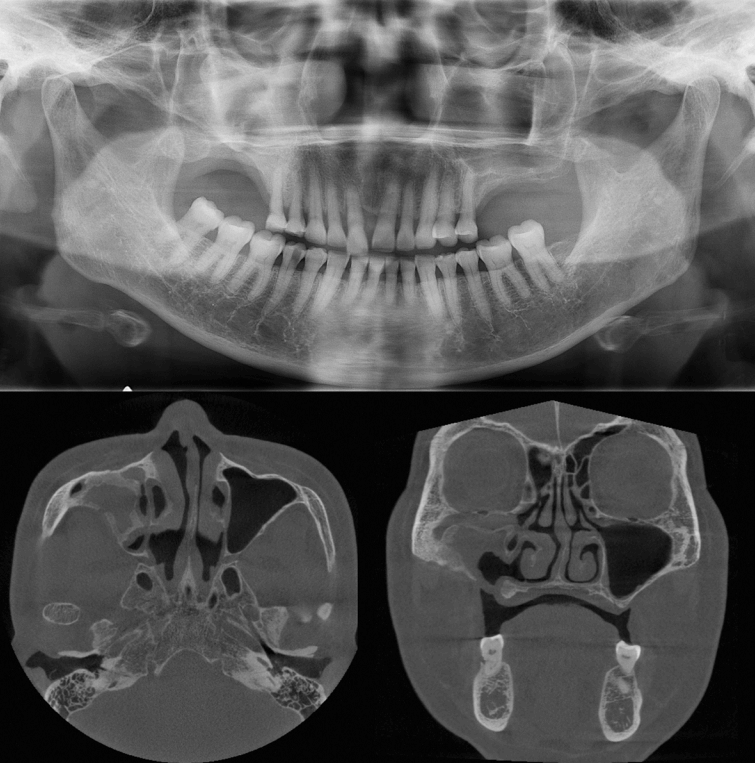

이 증례보고는 조선대학교치과병원 기관생명윤리위원회에서 승인 번호 CUDHIRB 2401 003으로 승인을 받았다. 72세의 여자 환자가 1년 전 우측 상악 제1,2 대구치 발거 후, 수개월 동안 지속해서 해당 부위에서 염증 삼출물이 나온다는 증상을 호소로 조선대학교 치과병원에 내원하였다. 처음 내원했을 때, 양측 상악 제1, 2대구치(#16,17,26,27)는 결손된 상태였고 임상 검사에서 발치 후 치유가 완전하게 진행된 정상 구강 점막의 형태를 관찰할 수 있었다. 환자는 전신 질환으로 고혈압과 당뇨가 있었으며, 안면부 외상이나 상악동 수술 등의 병력은 존재하지 않았다.파노라마방사선영상에서 우측 상악동 내부 대부분의 공간이 방사선불투과상으로 채워져 있는 것을 관찰할 수 있었다(Fig. 1). 또한 반대측과 비교하였을 때 우측 상악동 저의 경계가 분명하지 않고 치조골의 골밀도가 감소된 소견을 보였다. 추가적인 평가를 위해 cone-beam computed tomography(CBCT)에서 얻어진 영상을 axial, coronal, panoramic plane으로 재구성하였다. 재구성된 영상에서 우측 상악동 내부를 채우고 있는 장경 3.5 cm정도의 낭종 병소가 관찰되었으며, 상악동의 전방 및 후외측 골이 팽융되고 상악동의 후외측 경계와 상악 치조골이 병소에 의해 소실된 소견이었다(Fig. 2). 병소의 경계는 대체적으로 잘 구분되고 타원 형태의 구조를 보였다. 경계 부위에서는 비후된 형태의 경화성 골 변연이 관찰되었고 병소 내부에서는 불규칙하고 무정형의 석회화가 산재되어 있었다. 술후상악낭(postoperative maxillary cyst)과 석회화치성낭(calcifying odontogenic cyst)을 감별진단으로 고려하였다.본원 구강악안면외과에서 전신마취 하 구강 내 치조정측 접근을 통한 수술적 적출을 시행하였는데, 수술하면서 우측 상악동에서 농이 배출되는 양상과 육안상으로 볼 때 육아종처럼 보여지는 종괴(granulative mass)를 관찰할 수 있었다(Fig. 3). 수술 후 병리조직학적 검사 결과, 광범위한 골화를 동반한 콜레스테롤 육아종(cholesterol granuloma with massive ossification)으로 진단되었다(Fig. 4).환자는 수술 후 약 2주 정도 수술 부위에 대한 관리와 상악동의 배농 및 환기 상태의 유지를 위해 추가적인 처치를 받은 후 퇴원하였고, 수술 8개월 후 시행한 CBCT 검사에서 재발과 관련된 소견이 관찰되지 않았으며(Fig. 5) 현재까지 별다른 합병증 없이 추적 관찰 중이다.

Figure 1.

There is a haziness in the right maxillary sinus (*) with bony bulging at the posterior margin of the sinus and the bone density of the upper right alveolar bone is also reduced.